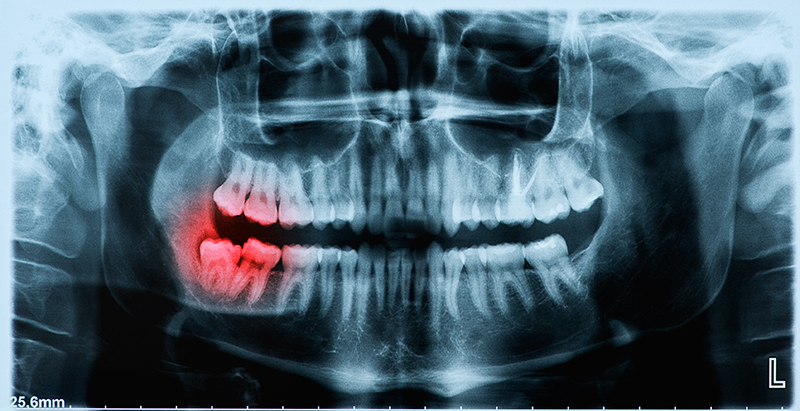

Yirmi yaş dişleri, en son süren dişler olduklarından, genellikle sürmeleri için gerekli yeri bulamazlar. Ancak, çürük vs. sebeplerle yirmi yaş dişleri sürmeden önce çenelerde başka dişler kaybedilmişse, bu durumda, yirmi yaş dişlerinin sürmeleri sağlanıp dentisyona kazandırılmaları faydalı olabilir. Tam olarak sürememiş yirmi yaş dişlerinin keser diş çapraşıklığı üzerinde sınırlı bir etkisi vardır. Ortodontik tedavi sonunda hekiminiz, yirmi yaş dişleri için çekim endikasyonu koymuşsa,bu işlemin, vakit geçirilmeden yapılması, tedavi sonuçlarının kalıcılığı açısından önemlidir.